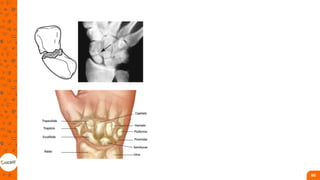

PUNHO

• Articulações radiocarpicas e

mediocárpica;

• Distal do radio: até 3 cm da

articulação radiocárpica;

• jovem masculina, em traumas de

alta energia, como quedas de

alturas, acidentes de trânsito e

atividades esportivas, mas

também idosos, população

predominantemente feminina,

em queda da própria altura;

• As fraturas distais de rádio podem ser

descritas como fraturas de Colles,

Smith, Barton ou Hutchinson,

dependendo das características da

lesão;

• O único achado característico é a

presença da deformidade em “dorso de

garfo”, comum na fratura de Colles;

• importância para a estabilidade do

punho, a destreza nos movimentos dos

dedos e a força de preensão e pinça da

mão

ESCAFOIDE

• É frequentemente a fratura mais

difícil de diagnosticar e de tratar.

Muitas fraturas não são visíveis

após o trauma, nos casos de

suspeita de fratura, os pacientes

devem ser tratados com

imobilização. Deve ser feito o

controle radiológico no período

de 2 a 4 semanas.

• Osteonecrose, pseudoartrose;

• pacientes normalmente têm dor

à palpação na tabaqueira

anatômica, nos movimentos

extremos do punho e na

compressão axial do polegar. O

edema e a equimose só estão

presentes nos casos de fratura –

luxação. A amplitude de

extensão pode estar limitada, e a

força de preensão palmar,

diminuída e dolorosa.